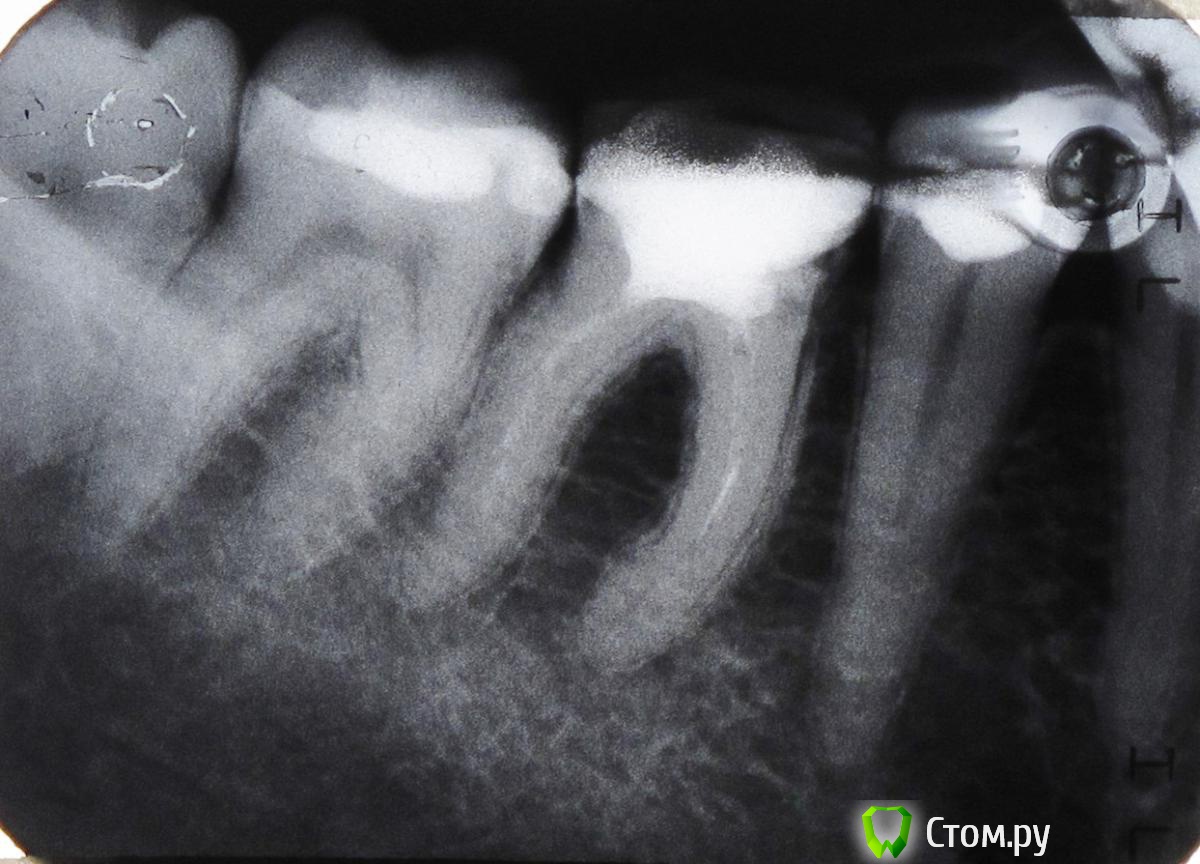

Maria2014 Опубликовано 15 января, 2014 Поделиться Опубликовано 15 января, 2014 Здравствуйте.На протяжении последних 2-3 месяцев постоянно возникает боль при жевании в районе нижних 7-8. Из-за этого жую только на одной стороне. В покое ничего не беспокоило.Последние 4 дня бепокоит боль в основании нижней челюсти (боль в кости, ниже корней зубов) с этой же стороны, но уже в районе 6. Боль в покое, а так же принадавливании снаружи. Усиливается на холоде.Сделала снимок, была у двух врачей-терпапевтов и у одного хирурга. Причину боли определить не могут. Предлагают лечить методом исключения, т.е. каждый зуб по очереди.Все указанные зубы пломбировались лет 10 назад.Назначили сделать еще простой снимок, на пленке.Несколько вопросов:1. Связана ли боль при жевании с болью в нижней челюсти, или это две разные проблемы?2. Связана ли боль в нижней челюсти с зубами, или есть какая-то другая причина?Завтра попробую здесь повесить обычный снимок.Спасибо! Ссылка на комментарий

Stomart Опубликовано 16 января, 2014 Поделиться Опубликовано 16 января, 2014 6-й зуб надо перелечивать, 5-й проверить на витальность. Ссылка на комментарий

red_butler Опубликовано 16 января, 2014 Поделиться Опубликовано 16 января, 2014 +1 к последнему посту. Провести холодовую пробу эндофростом (специальный газ в болончике) 5 и 7 зубов, повторное лечение корневых каналов и протезирование 6-го, и удалить зуб мудрости Ссылка на комментарий

Maria2014 Опубликовано 17 января, 2014 Автор Поделиться Опубликовано 17 января, 2014 Размещаю снимок.От чего же все-таки болит челюсть - от зубов, или причина иная? Никто из трех посещенных врачей не дал ответ на этот вопрос. Ссылка на комментарий

IvanK Опубликовано 17 января, 2014 Поделиться Опубликовано 17 января, 2014 Сделайте панорамный снимок. Думаю, что на 7 и 8 скрытый контактный кариес Ссылка на комментарий

ромашечка Опубликовано 17 января, 2014 Поделиться Опубликовано 17 января, 2014 . Мария, однозначно вам наверное ,никто не ответит. Начните с простого. У вас есть причины для боли во рту- 6 зуб перелечевание каналов, 7,8 лечение скрытого кариеса . Это как минимум. Без осмотра. Уберите эти причины. Если продолжит болеть челюсть- двигайтесь дальше. 1 Ссылка на комментарий